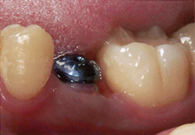

④ インプラント

| 治療前 | 治療後 | 治療後 |

主訴 |

虫歯を治したい。歯と銀歯を白くしたい。歯のないところにインプラントを入れたい |

治療期間 |

6か月 |

治療費 |

下顎のみ インプラント¥200,000×3本 チタンアバットメント¥50,000×3本 メタルセラミックス¥100,000×14本 合計¥2,150,000(税別) |

治療内容について |

全額的な治療を希望されて来院された患者さんです。 奥歯を失ったことによって噛み合わせが低くなり、前歯が強く噛み合うようになって歯が咬耗したり、差し歯の脱落を繰り返していました。 このような咬合崩壊例では、噛み合わせの支えとなる奥歯をしっかりと入れることが何よりも重要となります。前歯は、奥歯の支えがあることで長持ちするのです。 |